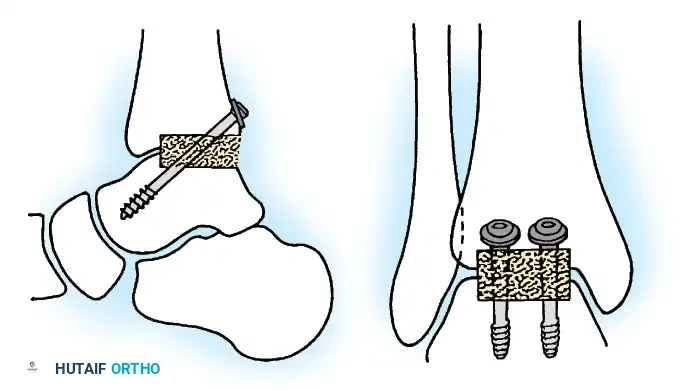

Internal fixation is currently the preferred method for uncomplicated ankle arthrodesis due to higher union rates, superior patient comfort, and the elimination of pin-tract infections. Biomechanical studies demonstrate that crossed, large-diameter (6.5 mm or 7.3 mm) cannulated cancellous screws provide exceptional resistance to shear and torsional forces.

A standard construct involves two or three screws:

1. A "home run" screw directed from the posterior malleolus into the anterior neck of the talus.

2. A screw from the medial malleolus into the lateral body of the talus.

3. A screw from the anterolateral tibia into the medial talar body.

For complex hindfoot reconstructions, specialized plating systems, including anterior or lateral locking plates, can be utilized to supplement screw fixation, particularly when structural allografts are required to restore limb length.